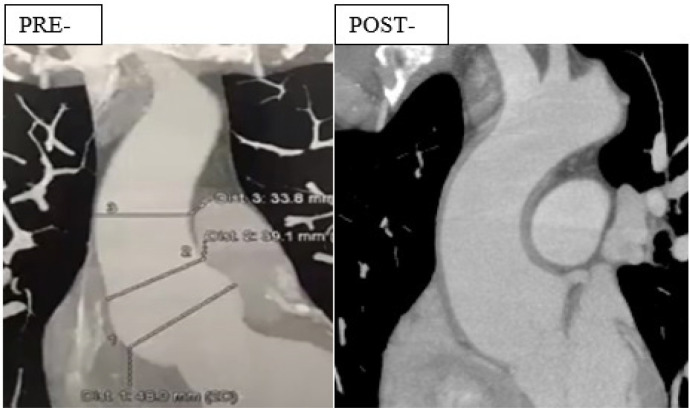

Methods: This report presents the initial clinical experience with the ExoVasc® PEARS implant in the Americas, encompassing 10 patients (six males, age range 30 - 52 years, mean age 37.8 years) diagnosed with aortic root aneurysms. Indications for PEARS included Marfan syndrome (eight patients, including one reoperation), bicuspid aortic valve (two patients, including one with anomalous coronary artery), and associated valvular dysfunction. Cardiopulmonary bypass was utilized in four cases.

Results: No major adverse postoperative events were observed. Postoperative recovery was generally uneventful, with minor complications, including pericarditis and atrial fibrillation, successfully managed with medical therapy. Aortic dimensions remained stable at 30-day and one-year follow-ups.